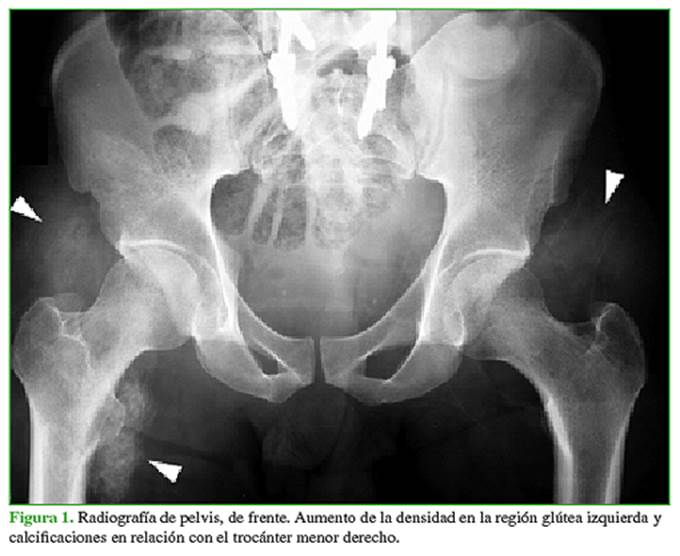

La resonancia magnética con medio de contraste muestra, en las secuencias, pequeñas imágenes de baja señal en el trocánter menor derecho, leve refuerzo poscontraste. Hay un discreto edema en las secuencias T2. En la región glútea izquierda, la señal en la secuencia T1 es intermedia y, en la secuencia T2, es alta, con marcado refuerzo del medio de contraste (Figura 2). La tomografía computarizada revela calcificaciones maduras en relación con el músculo psoas ilíaco derecho y pequeñas calcificaciones periféricas en la región glútea izquierda (Figura 3).